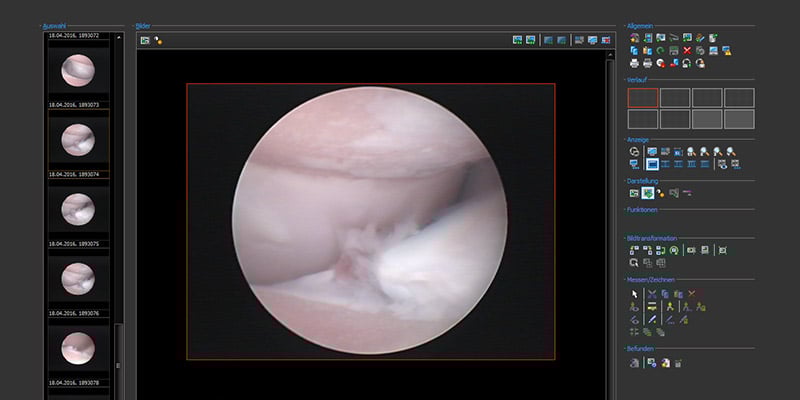

Arthroskopie:

Arthroskopie ist der sogenannte Gold Standard bei der Untersuchung der inneren Gelenkauskleidung. Dieser Schlüssellocheingriff unter Narkose ermöglicht es uns, einen Blick mit der Lupe auf die Beschaffenheit der Knorpelflächen und der inneren Gelenkhaut zu werfen und gleichzeitig eine Behandlung des Gelenks vorzunehmen.

Durch diesen minimalinvasiven Eingriff ist die Belastung Ihres Hundes post OP auf ein Minimum reduziert und eine schnelle Rehabilitation binnen weniger Tage zu erreichen.